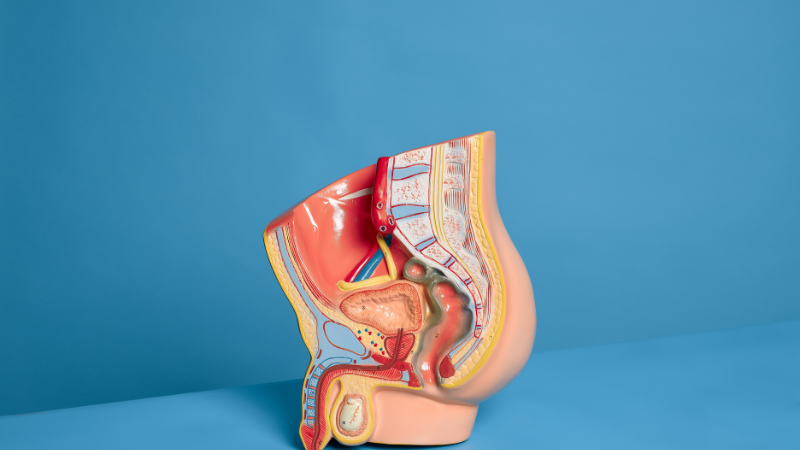

Why Your “Internal Brake” is Failing

Most men try to last longer by distracting themselves—thinking about work or math—but that actually makes things worse. Why? Because you’re ignoring the biological signals. To gain better sexual control, you need to train your pelvic floor and your brain to handle high levels of arousal without hitting the “eject” button.

Phase 1: Waking Up the PC Muscle (Weeks 1-2)

The Pubococcygeus (PC) muscle is your internal brake. If it’s weak or too tense, you lose control.

How to Find Your PC Muscle

- The “Stop-Pee” Test: Next time you’re in the bathroom, try to stop the flow of urine mid-stream. The muscle that flexes is your PC muscle. (Do this once to find it, not as a regular exercise).

- The Lift: Imagine your pelvic floor is an elevator. Try to “lift” it up toward your belly button.

The Routine: Perform 3 sets of 10 “squeezes” daily. Hold for 3 seconds, relax for 3. This builds the foundation for pelvic floor endurance.